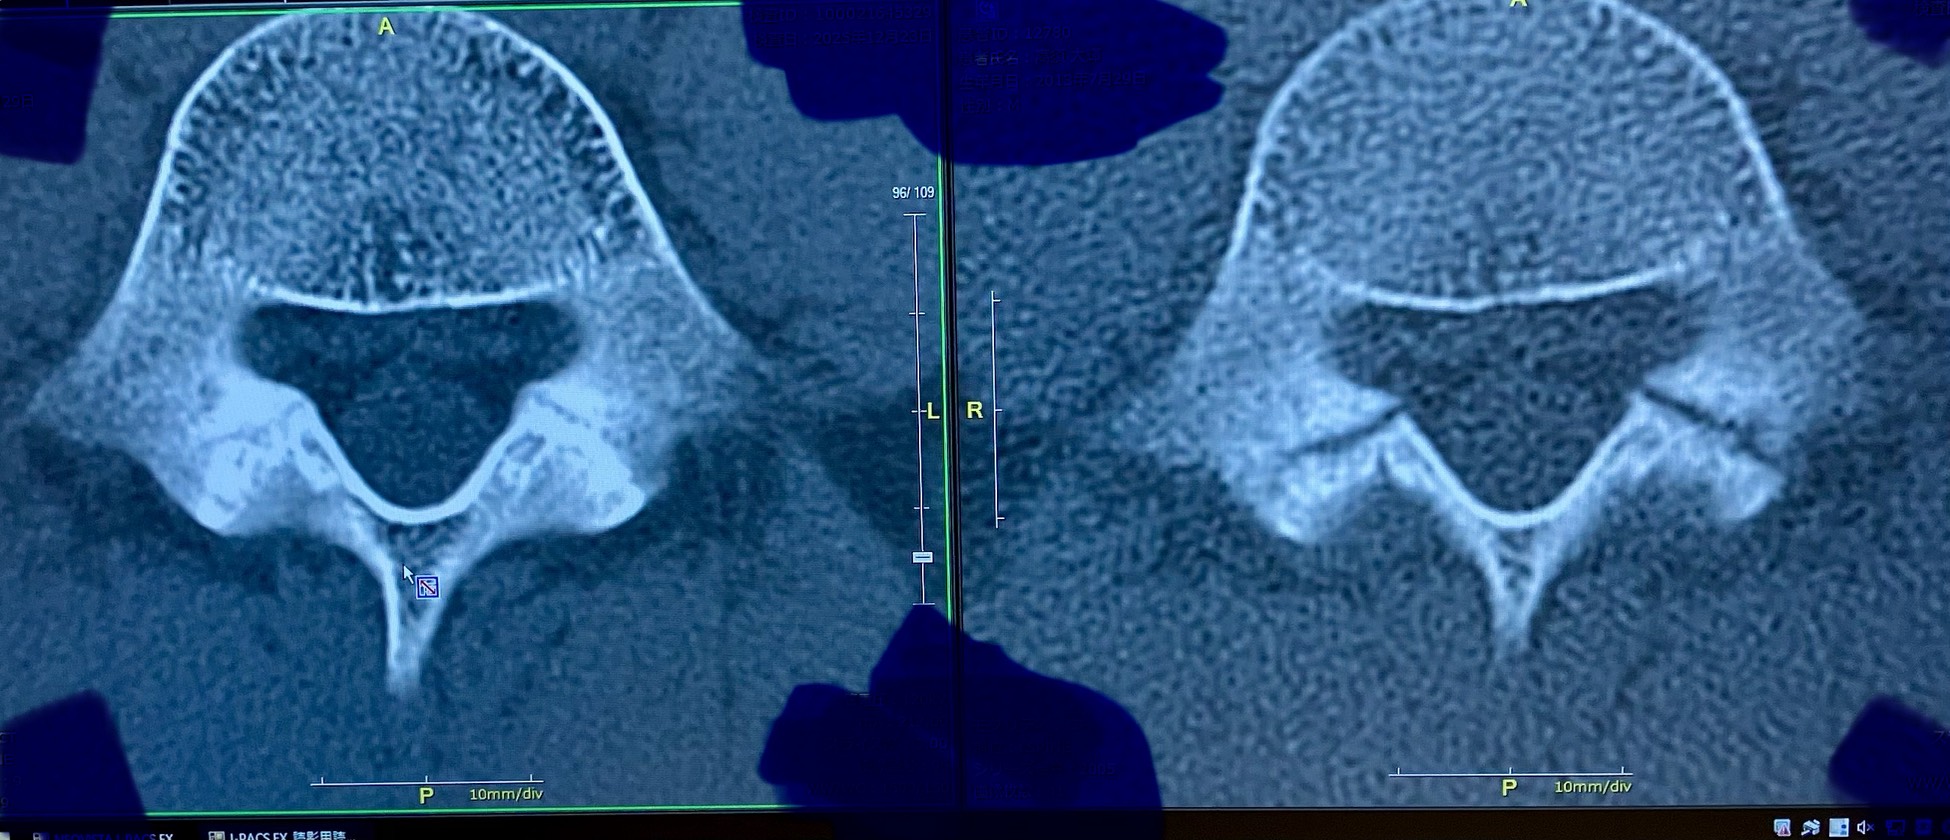

腰椎分離症・参考画像

右が腰椎分離症、発見時、左が、オステオトロンを3ヵ月使用とコルセット固定での画像になります。画像、右の右側の骨は完全に離れていて、整形外科からは、これは付かないと言われたそうです。最初、お電話を頂いた時は、半信半疑、でも、もしかしたらの期待で、オステオトロンをレンタルされた感じの記憶が有ります。3ヵ月後、画像を送って頂き、整形外科からは、奇跡だと、言われたそうで、お電話で少しお話しをしましたが、信じて良かったと喜んで頂きました。この瞬間が、信じて頂いてありがとうと、私達も嬉しい思いです。

同じ悩みの方の参考になればと、画像を提供して頂きました。オステオトロンを返却時、お手紙も頂いたので掲載させて頂きます。